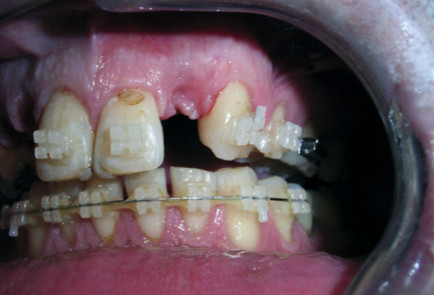

Mr H came to the Surbiton Smile Centre ® initially with the problem of a loose bridge. He avoided smiling as his teeth had been damaged in a rugby game several years previously causing his front teeth to be shunted forward. He had also lost a tooth on the upper right side, which had been replaced by a cantilever bridge supported by his top-right canine.

Unfortunately, this canine was fractured, and the entire bridge fell out. Upon examination it was found that his upper-left incisor was also infected and needed to be extracted. Mr H had developed the habit of clenching his teeth, which had over the years, worn down the surfaces of all his teeth.